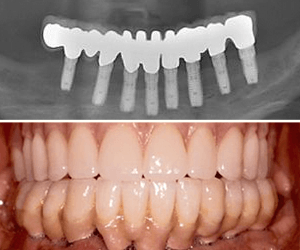

Implants